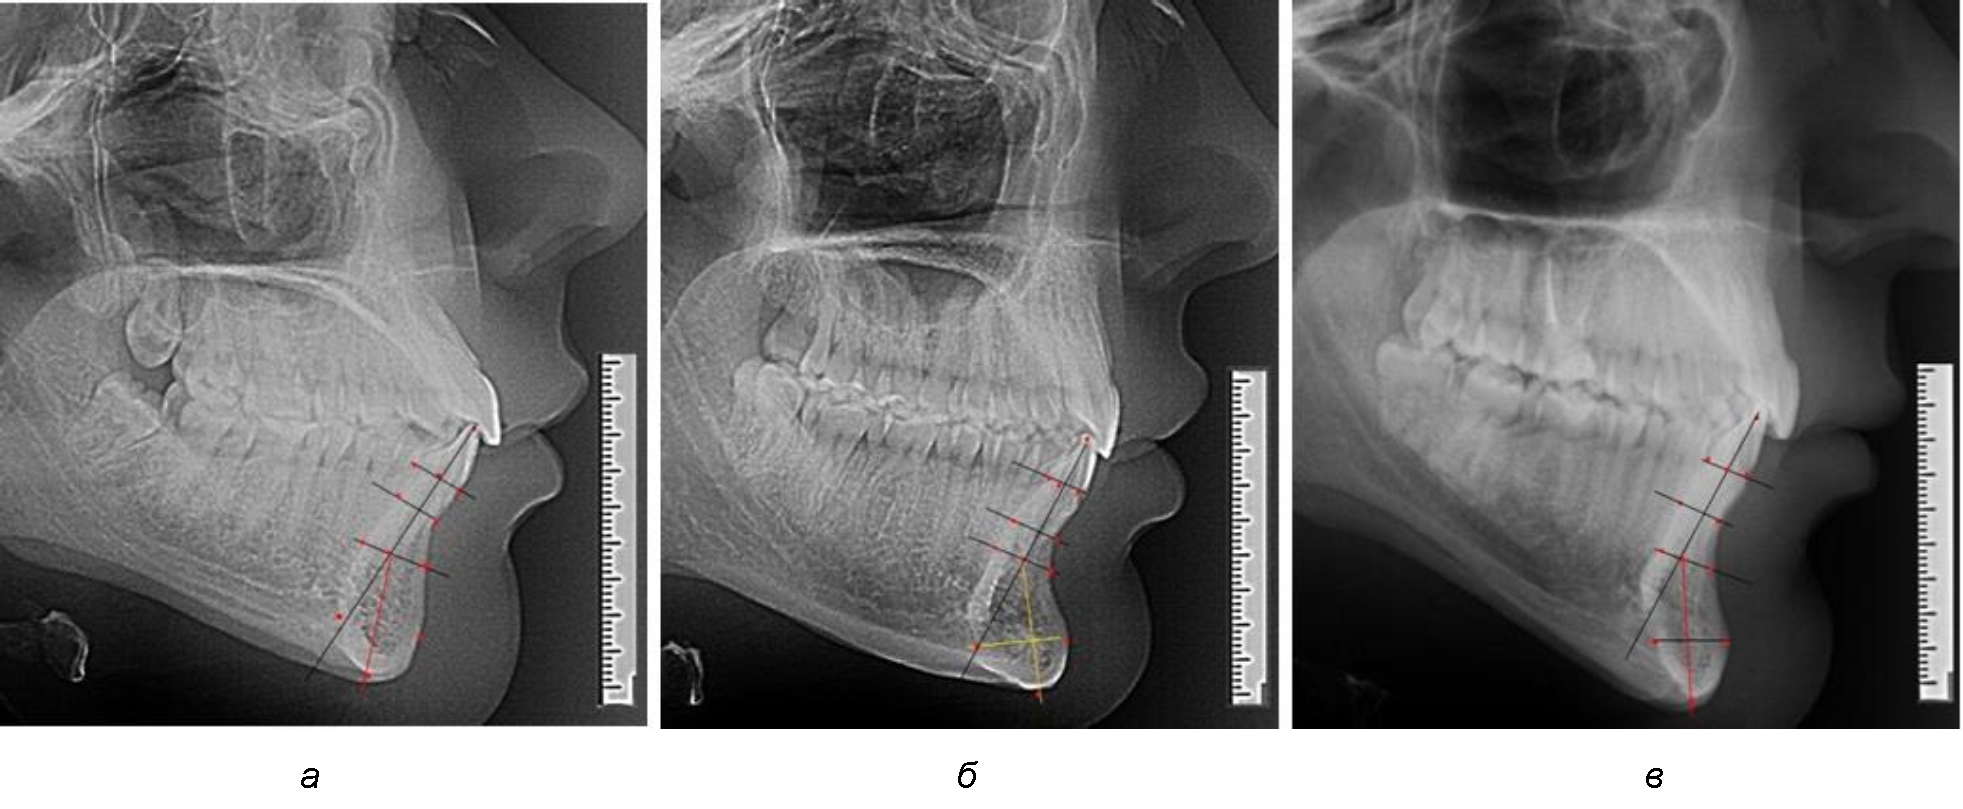

На нижнем контуре подбородочного выступа определяли положение ментальной точки Me. Линия, соединяющая апикальную точку с ментальной, определяла высоту подбородочного выступа тела нижней челюсти. Высота зубочелюстного сегмента IsL–Ме измерялась от резцовой до подбородочной точки. Вертикальная линия Ap–Me делила подбородочный выступ на две части: переднюю и заднюю (рис. 1).

Рис. 1. Ориентиры для исследования нативных препаратов (а) и рентгенограмм (б) резцового нижнечелюстного сегмента

Сагиттальные размеры зубоальвеолярной части сегмента определялись между точками Bsm и Bsm', в апикальной части сегмента – B и B'. В подбородочной части сегмента из передней выступающей точки подбородка Pog проводили линию перпендикулярно к линии Ар–Ме с определением точки Pog'. Расстояние Pog–Pog' определяло ширину подбородочного выступа.

Рис. 3. Варианты среднего (а), широкого (б) и узкого (в) нижнечелюстного резцового сегмента